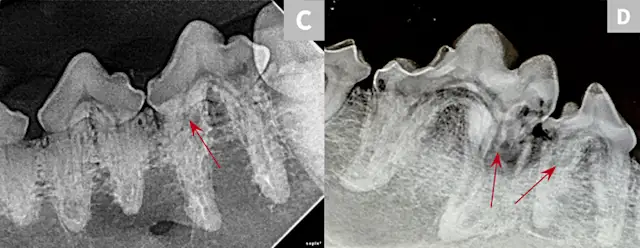

FIGURE 1: Periapical lucency

Periapical lucency develops secondary to bone loss around the tooth root caused by endodontic, neoplastic, or periodontal disease. In this dog, periapical lucency of the maxillary first and second molars (red arrows) developed secondary to periodontal disease. Periapical lucency secondary to endodontic disease (caused by exposure of the pulp from a slab fracture [blue arrow]) is also present surrounding the roots of the right maxillary fourth premolar (white arrow).

Observation of marked mobility of the molars would be expected on anesthetized examination. In this dog, the maxillary fourth premolar would likely not be mobile, as there is still bone surrounding the root apices. Extraction of the maxillary fourth premolar and first and second molars is indicated.